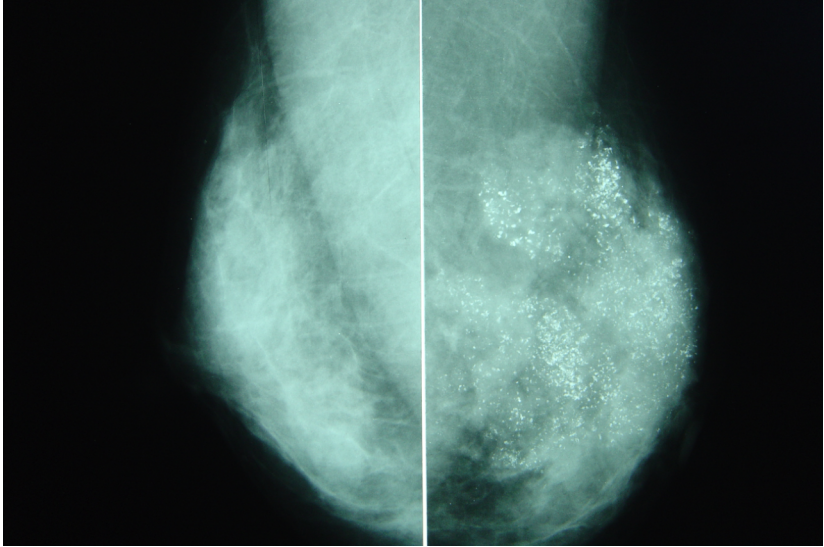

乳腺钼靶片:乳腺恶性钙化